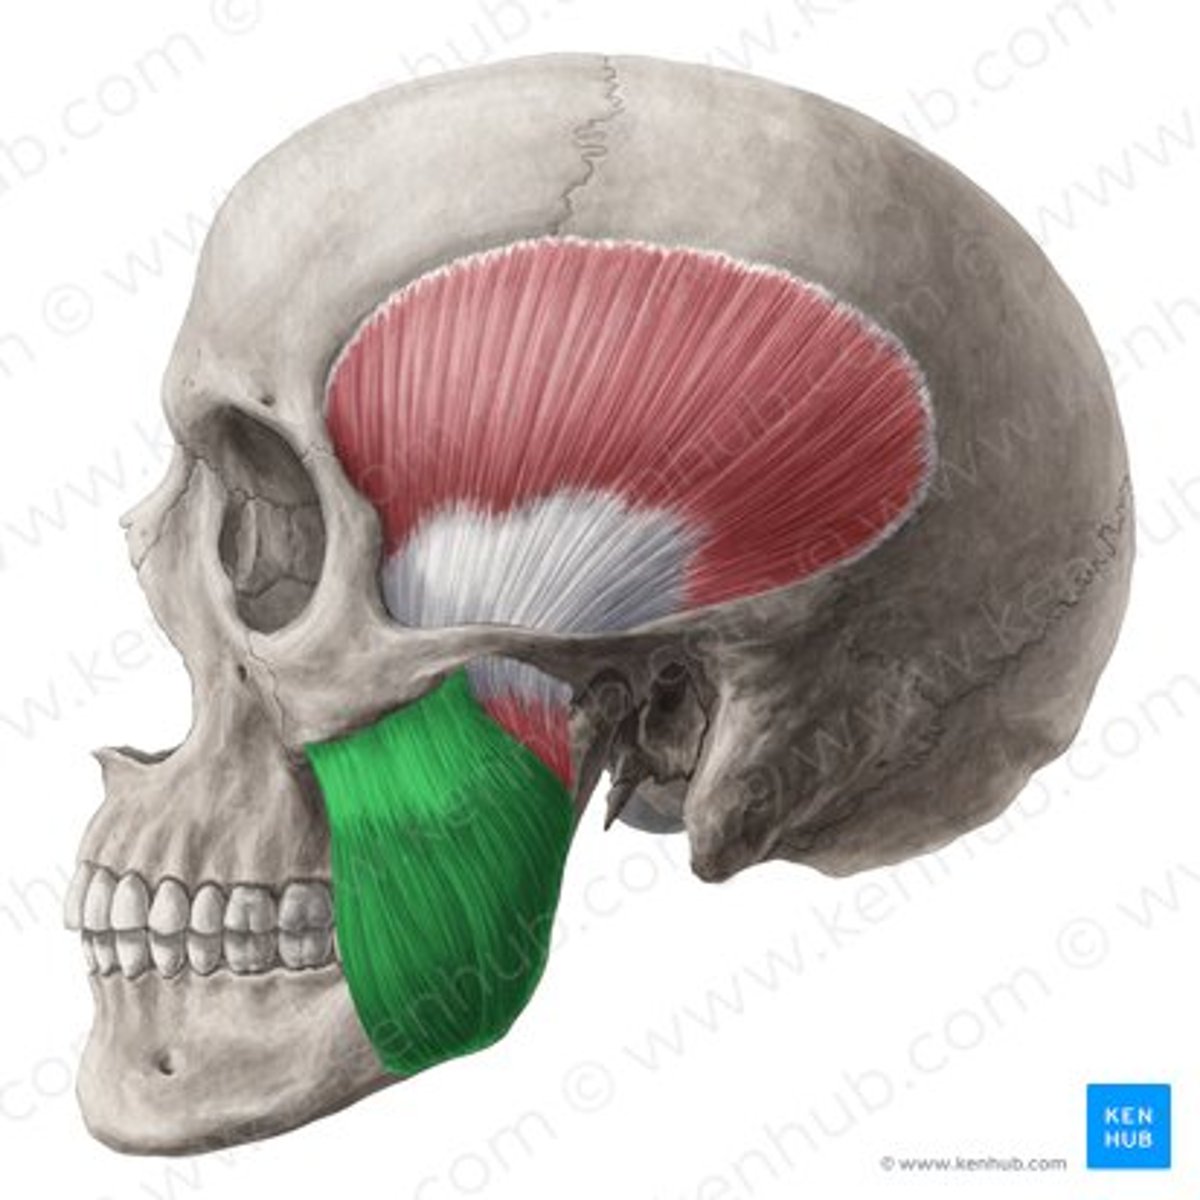

deep masseter

superficial masseter

temporalis

lateral pterygoid

lateral pterygoid, superior part

lateral pterygoid, inferior part